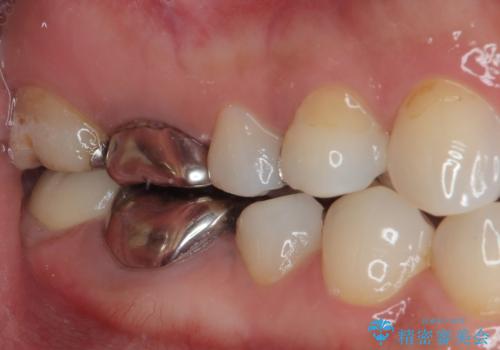

見た目、機能面共に満足していただけました。

今後もメンテナンスで通ってもらいながら、治療が必要になってきたところは順次行っていく予定です。

また咬み合わせが強いためナイトガードを使ってもらう予定です。